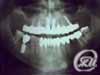

Implantology - explanation what is implantology, before and after implantation.